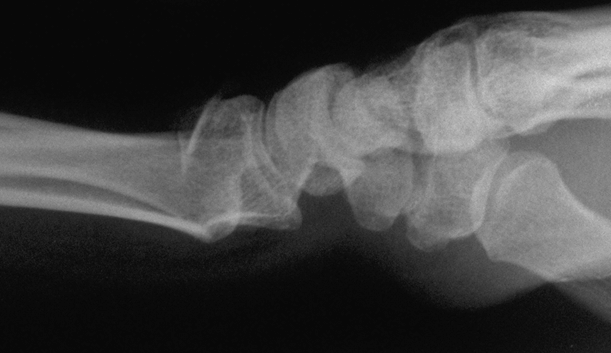

Case 1 Injury